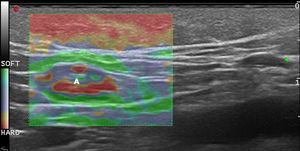

Elastografía de la piel normal y los anejosLa dureza de la piel sana varía en función del estrato cutáneo estudiado. La dermis es una estructura de rigidez superior al tejido celular subcutáneo16 (figs. 2a,b). En el tejido celular subcutáneo, los septos presentan mayor rigidez que los lobulillos grasos. Los vasos sanguíneos son estructuras poco rígidas, al igual que los nervios periféricos, en comparación con el tejido celular subcutáneo circundante16.

a) Elastografía de strain de la piel normal. Obsérvese el ratio de rigidez de dermis y la grasa SR=1,86 que indica que la dermis es más dura que el tejido celular subcutáneo.

E: epidermis; D: dermis; TCS: tejidocelular subcutáneo.